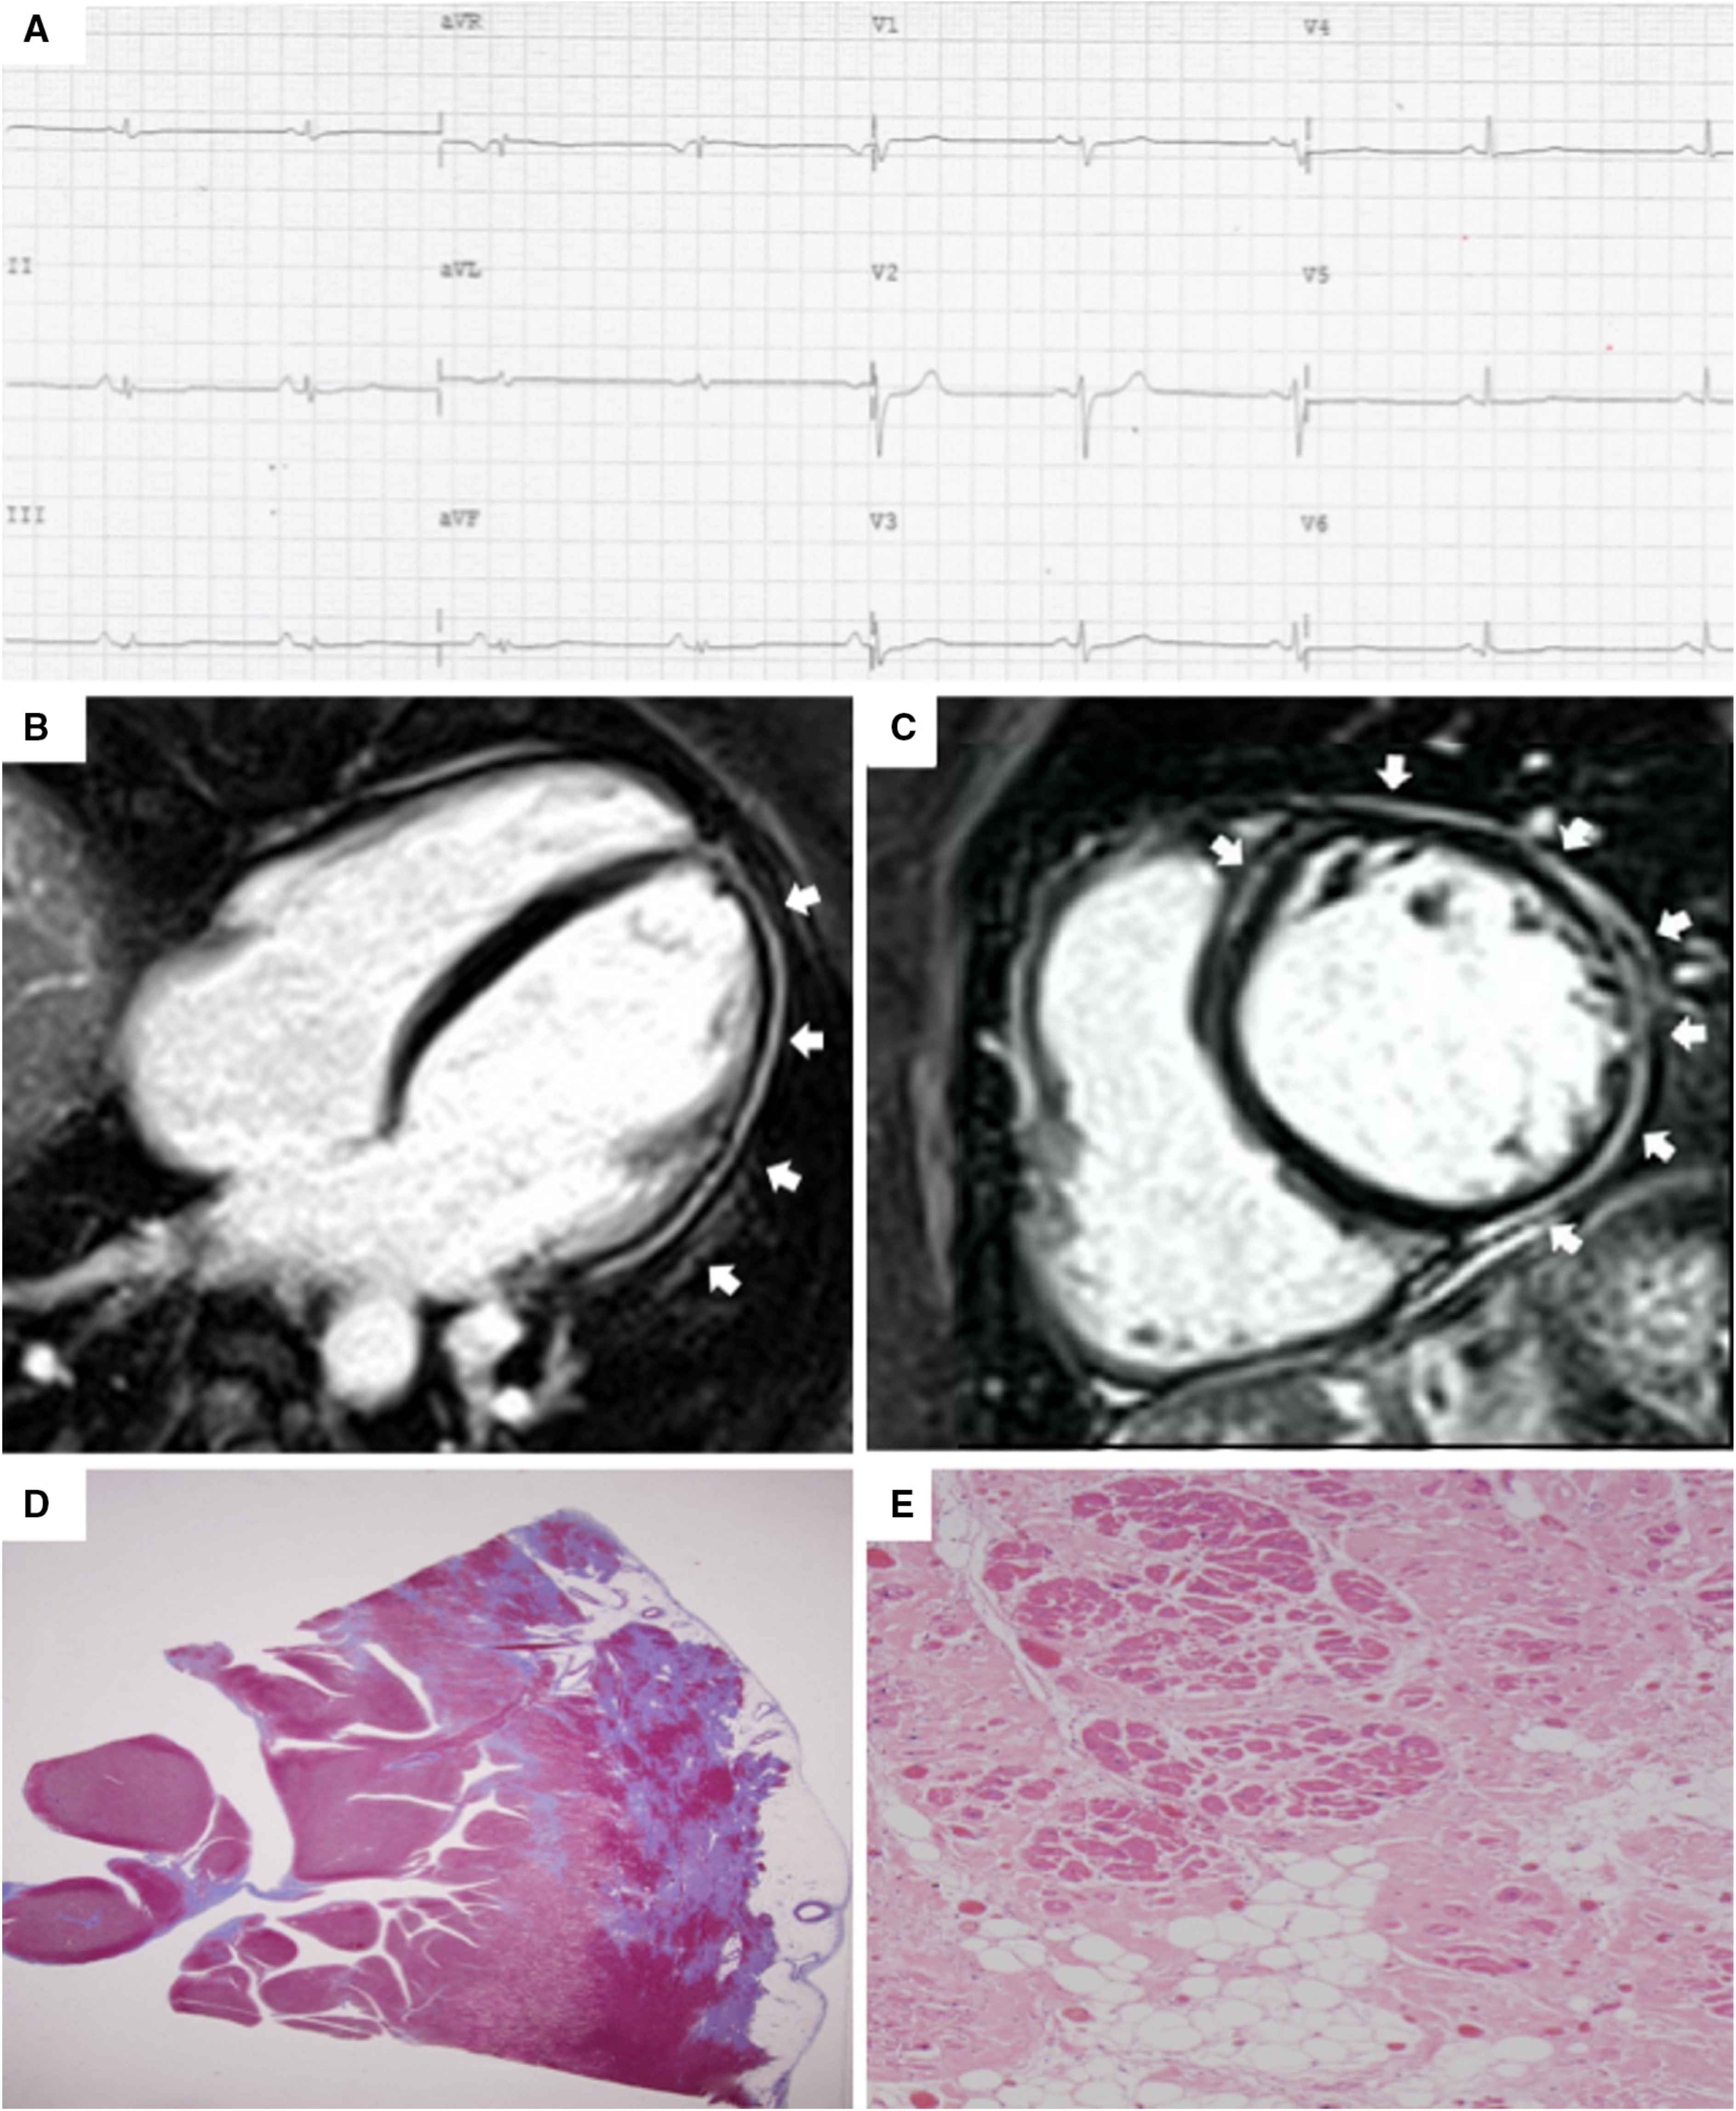

The presence of low QRS voltages in limb leads (peak-to-peak QRS amplitude

Fig. 5.Clinical features of biventricular ACM. Basal ECG and CMR findings in a 28-year-old elite athlete. ECG revealed low QRS voltages in limb leads (A). Exercise testing demonstrated PVBs with a RBBB/superior axis morphology, isolated and in couples. CMR cine-sequences showed hypokinesis of the mid-apical lateral wall and multiple small bulging of the RV free wall (B, four-chamber view). The PD-TSE sequences revealed epicardial fatty infiltration of the lateral and inferior LV walls (C, four-chamber view). Post-contrast sequences on CMR demonstrated a subepicardial stria of LGE involving the antero-lateral, infero-lateral and inferior LV walls (D, short- axis view) and also the RV inferior wall (E, RV inflow-outflow view). The diagnosis was “definite biventricular ACM”. ACM, arrhythmogenic cardiomyopathy; CMR, cardiac magnetic resonance; LV, left ventricle; PVBs, premature ventricular beats; PD-TSE, proton density-turbo spin echo; RBBB, right bundle branch block; RV, right ventricle. Adapted from Zorzi et al. [38].